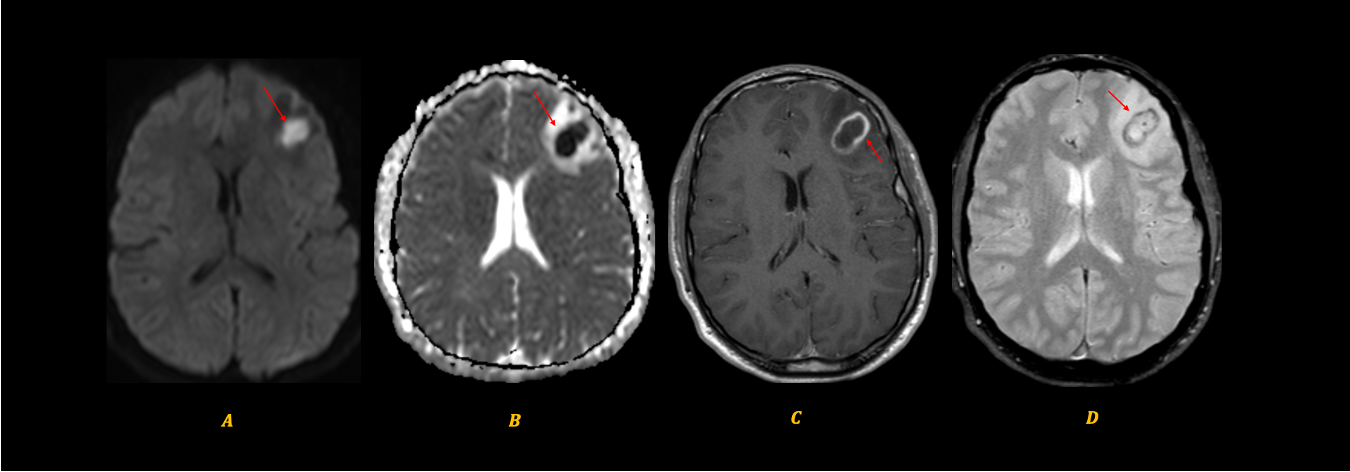

A 67-year old woman with chronic hypertension, hyperlipidemia and diabetes mellitus non-compliant to medication presented with a 10-day history of recurrent visual phenomena in the left visual field. She described stationery multi-coloured flashing lights which decreased in intensity, brightness and size after 3 minutes. She was alert and conscious during attacks. There was no limb jerking. Neurological examination was normal with no visual field defect. Capillary glucose was 28.1 mmol/L, Hba1c 9% and B-hydroxybutyrate < 0.1. She was treated with actrapid 8 units, glipizide 5 mg BD and empagliflozin 12.5 mg OM. Interictal electroencephalogram was normal with no epileptiform activity. Brain magnetic resonance imaging revealed restricted diffusion in the right occipital cortex with corresponding cortical thickening and increased FLAIR signal with subtle hypodensity on GRE sequence. Her visual symptoms improved dramatically with hydration and diabetic control. She was treated with a short course of keppra. One month later repeat MRI brain showed resolution of the DWI and FLAIR abnormalities.

Initial dwi

D